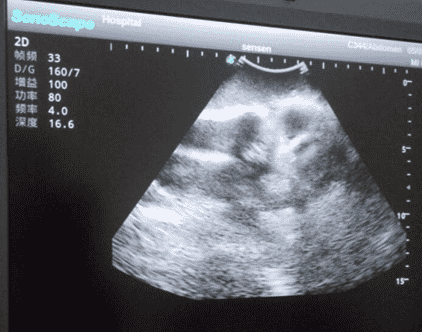

2)   Real clinical ultrasound images with clear anatomical structures like femur, joint cavity, etc.